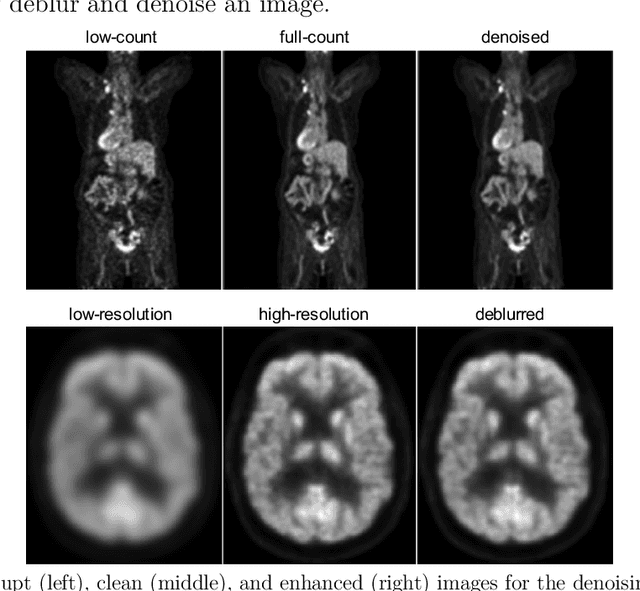

Abstract:High noise and low spatial resolution are two key confounding factors that limit the qualitative and quantitative accuracy of PET images. AI models for image denoising and deblurring are becoming increasingly popular for post-reconstruction enhancement of PET images. We present here a detailed review of recent efforts for AI-based PET image enhancement with a focus on network architectures, data types, loss functions, and evaluation metrics. We also highlight emerging areas in this field that are quickly gaining popularity, identify barriers to large-scale adoption of AI models for PET image enhancement, and discuss future directions.